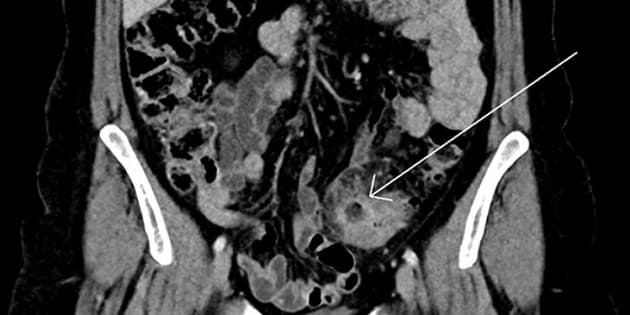

CT-billede af ukompliceret divertikulitis i colon sigmoideum med lokal inflammation og stranding omkring et divertikel (pil).

Ukompliceret akut divertikulitis er karakteriseret ved forekomst af lokaliseret inflammation med eller uden små intramurale abscesser i sigmoideum, mens ved kompliceret divertikulitis ses perikoliske abscesser, peritonitis, obstruktion og fistulering. Statusartiklen af Dichman og Shabanzedah gennemgår ætiologi, patofysiologi, diagnosticering og behandling af ukompliceret divertikulitis. Forfatterne konkluderer, at tilstanden ikke bør rutinemæssigt behandles med antibiotika.